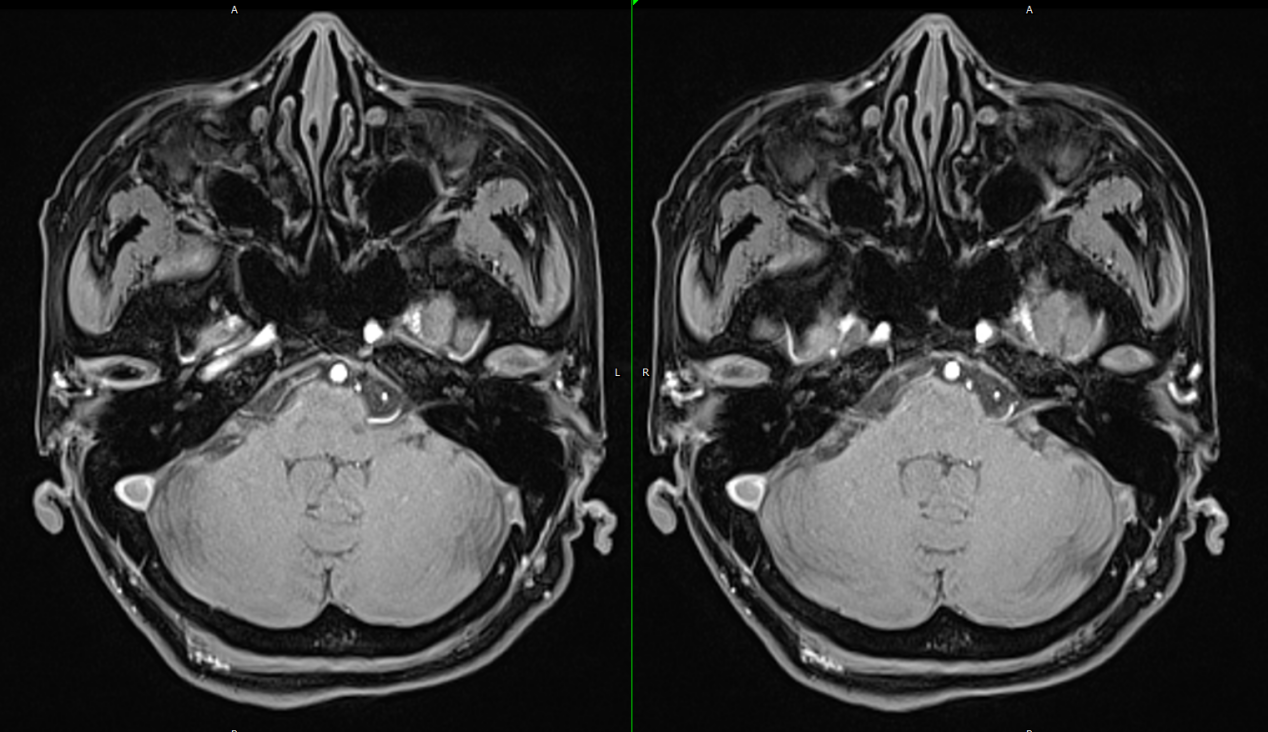

蔡医生在门诊看到彭女士的时候,第一印象是憔悴,耳鸣困扰、睡眠不足让彭女士看上去比实际年龄还苍老几岁。听了彭女士的主诉后,蔡医生让其去做面听神经MR检查,结果提示听神经有血管伴行和压迫。这下,困扰彭女士许久的耳鸣终于找到病因了,就是听神经压迫。为了解除听神经压迫,蔡医生建议彭女士做听神经微血管减压术,彭女士和家人商量后,同意手术。

微血管减压术不用大开颅,只需在患者耳后切口,开一小骨孔开颅,把仪器探进去,进入桥脑池找到听神经。在显微镜下可见小脑前下动脉行走于面听神经之间并压迫听神经,蔡医生将这根血管移开并在听神经与血管之间植入薄层垫片,这个手术就完成啦。

耳鸣的原因多种多样,多数为内耳道病变或听神经病变所致,找到病因后就可以对症治疗。但是有一类耳鸣病人,内耳或颅内的各项检查都未能发现病变,普通的治疗无效,就跟彭女士一样。这个时候就应该考虑是否存在血管压迫听(耳蜗)神经的可能,做一个面听神经的磁共振(MR)即可发现问题,而且这类患者常表现为高频耳鸣或高频混合低频耳鸣,伴有波动性、缓慢进展的听力下降,有些病人还伴有位置性眩晕。